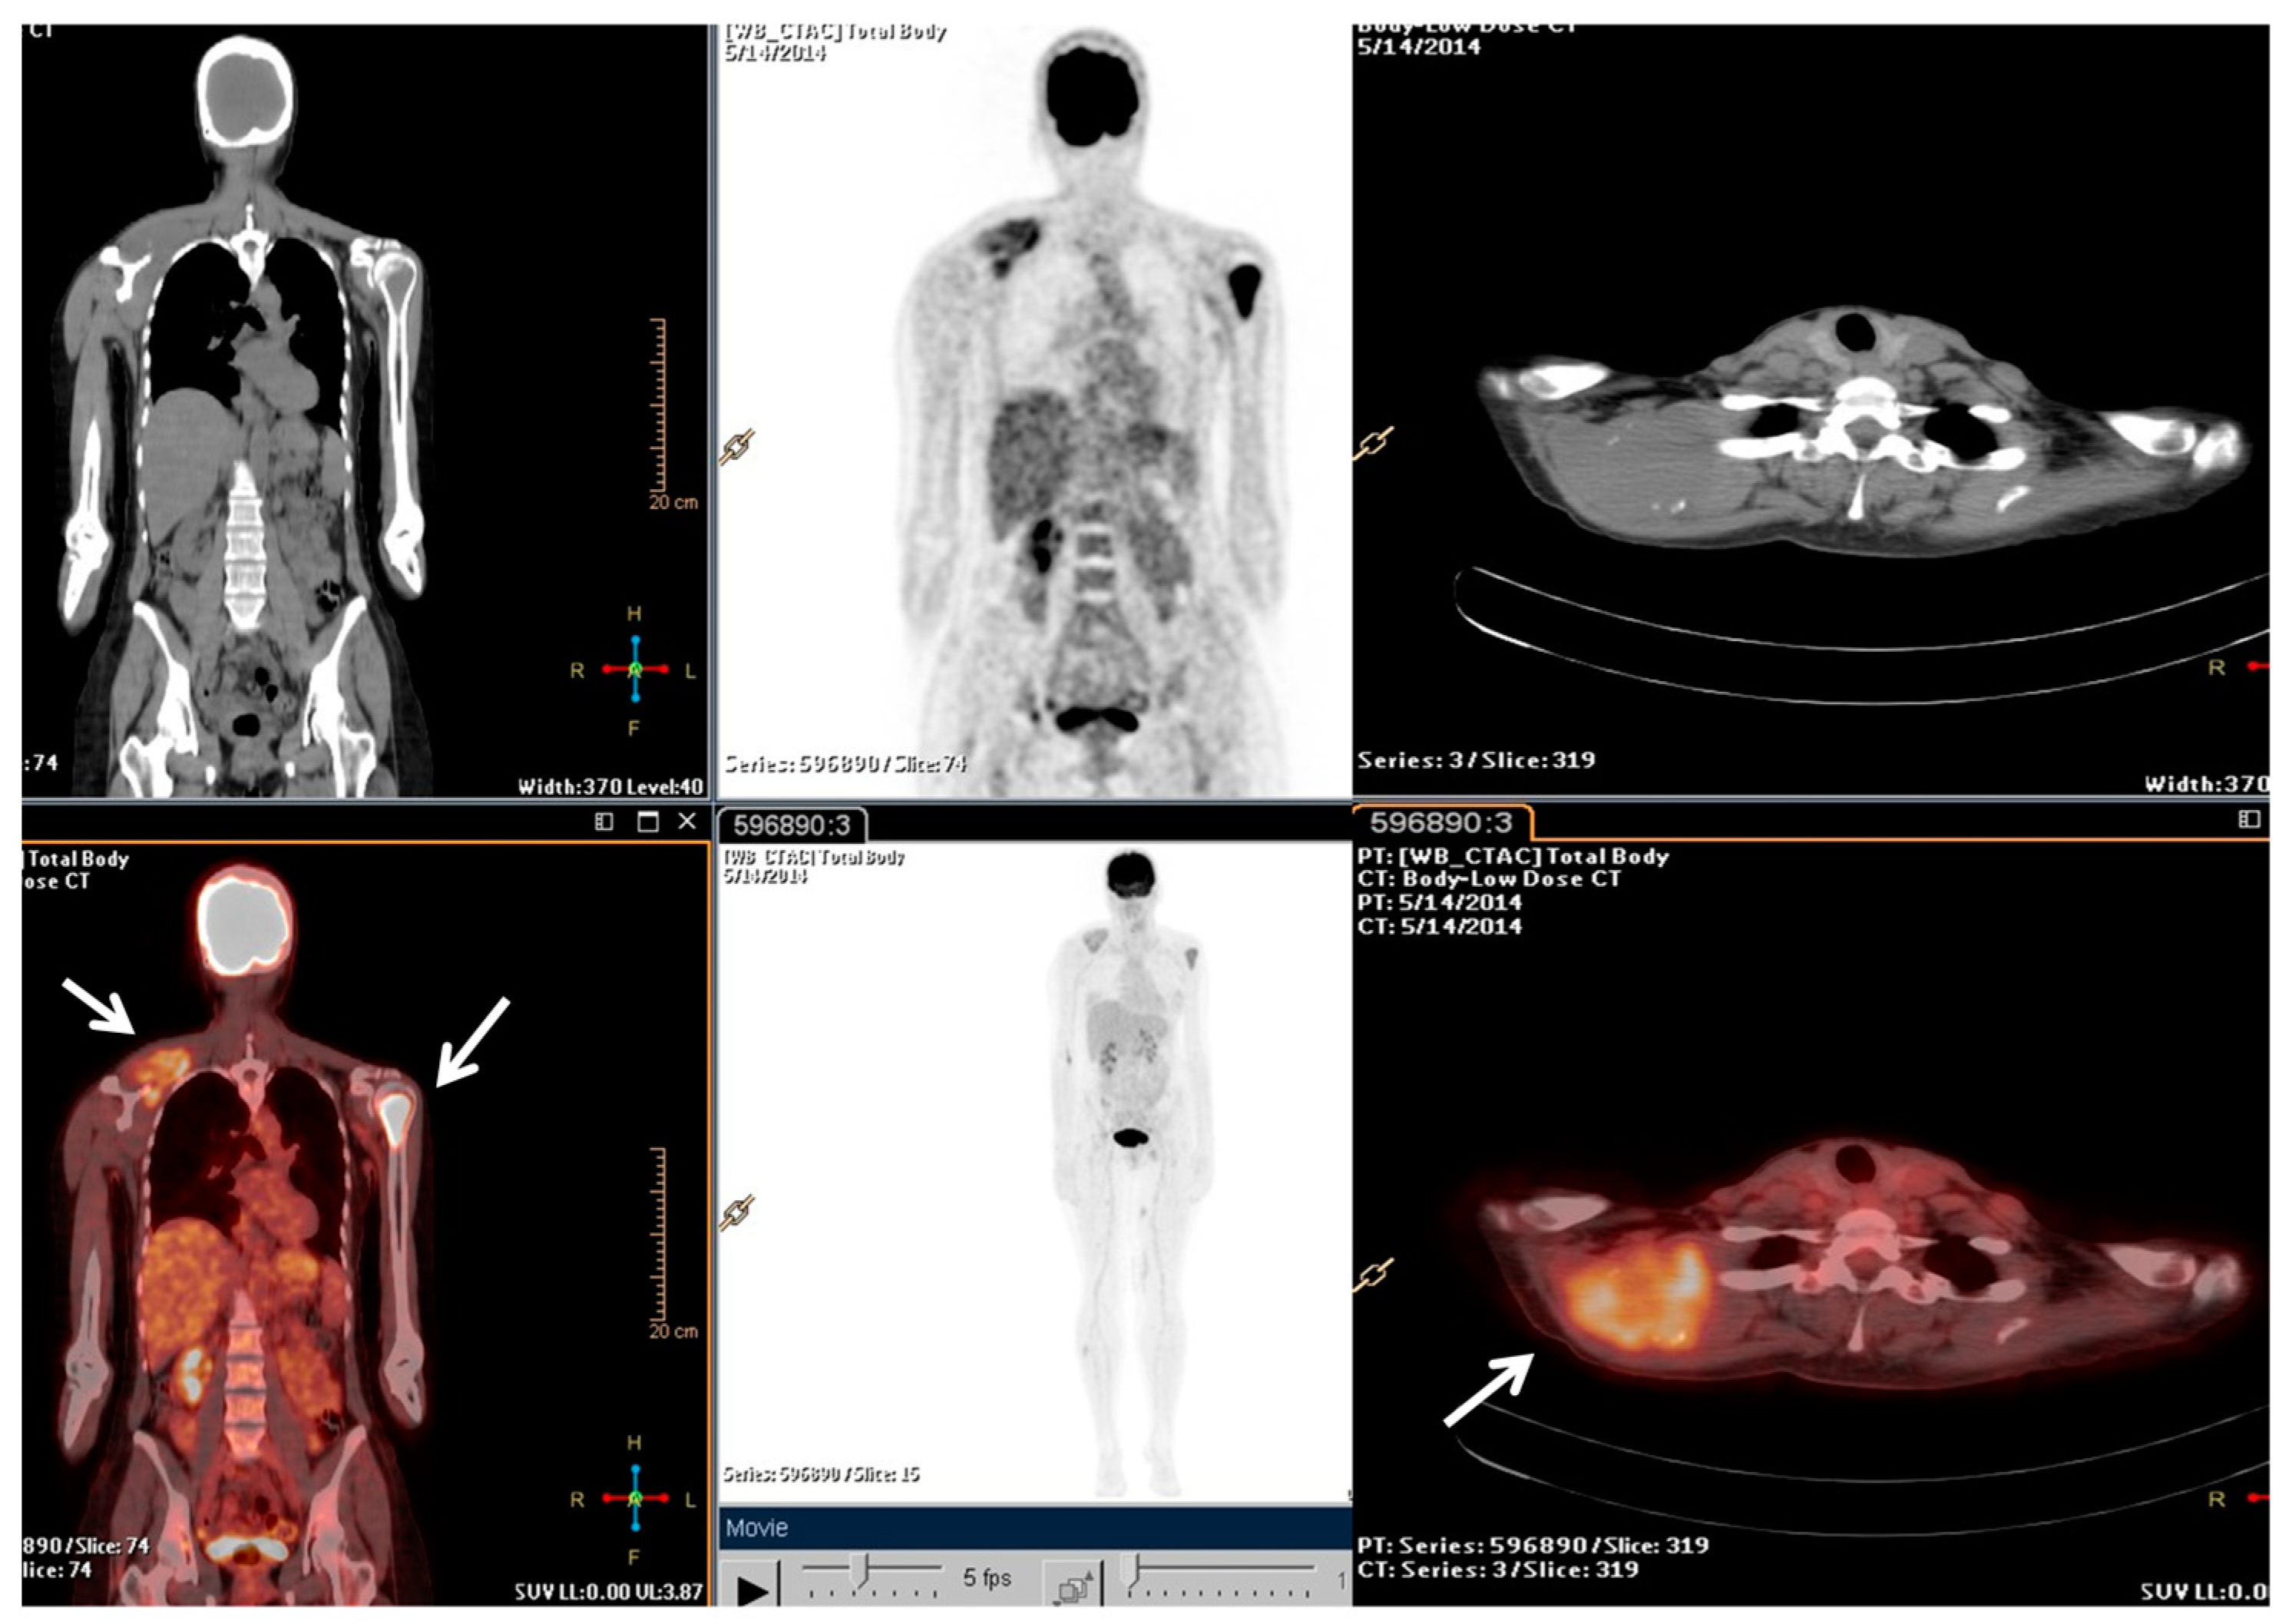

Following the stage of the disease (pT1b, IA) and grade (G2), a clinical–instrumental follow-up was initiated. Nine months after the initial diagnosis, a PET/CT scan detected a large, metabolically active solid mass involving the right scapula and the periscapular muscles, as well as the involvement of cervical spine segment and the left proximal humerus (Figure 1).

Figure 1.

The F-18 Fluorodeoxyglucose (FDG) Positron Emission Tomography/Computed Tomography (PET/CT) performed at baseline of radiotherapy treatment, nine months from the diagnosis. The main tumour lesions are indicated by white arrows.